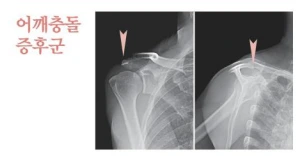

어깨 충돌증후군

3.PNG

어깨충돌증후군은 어깨 힘줄인 회전근개와 그 위에 있는 견봉이 반복적으로 부딪히면서 염증이 발생하는 것입니다. 어깨를 높이 들어 올리거나 과도하게 무리하는 경우, 장시간 컴퓨터를 사용하는 경우에 발생할 수 있습니다. 어깨 힘줄 위 덮개뼈의 이상으로 생기는 경우도 있답니다.

하지만 어깨충돌증후구는 유착성 염증 질환은 아니어서 수면을 취할 때 극심한 통증은 없는 편입니다. 또한 초기에는 큰 통증을 느끼지 못하실 가능성이 높아요. 보통 팔을 앞쪽으로 들 때나 위쪽으로 들 때 통증이 발생하는데요. 팔을 올리고 내릴 때 무언가에 걸리는 듯한 통증이 발생하고 소리가 나기도 하는 특징도 있습니다.